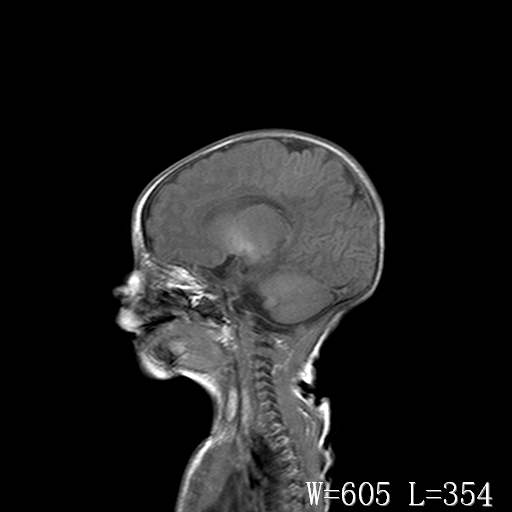

标题: PED3338:脑部病变?

男,4天,发复抽搐1天。

新生儿正常颅脑

脑干形态欠规则,信号增高,不知怎么解释?

脑干背侧面t1高信号是,新生儿正常已经髓鞘化好的部位